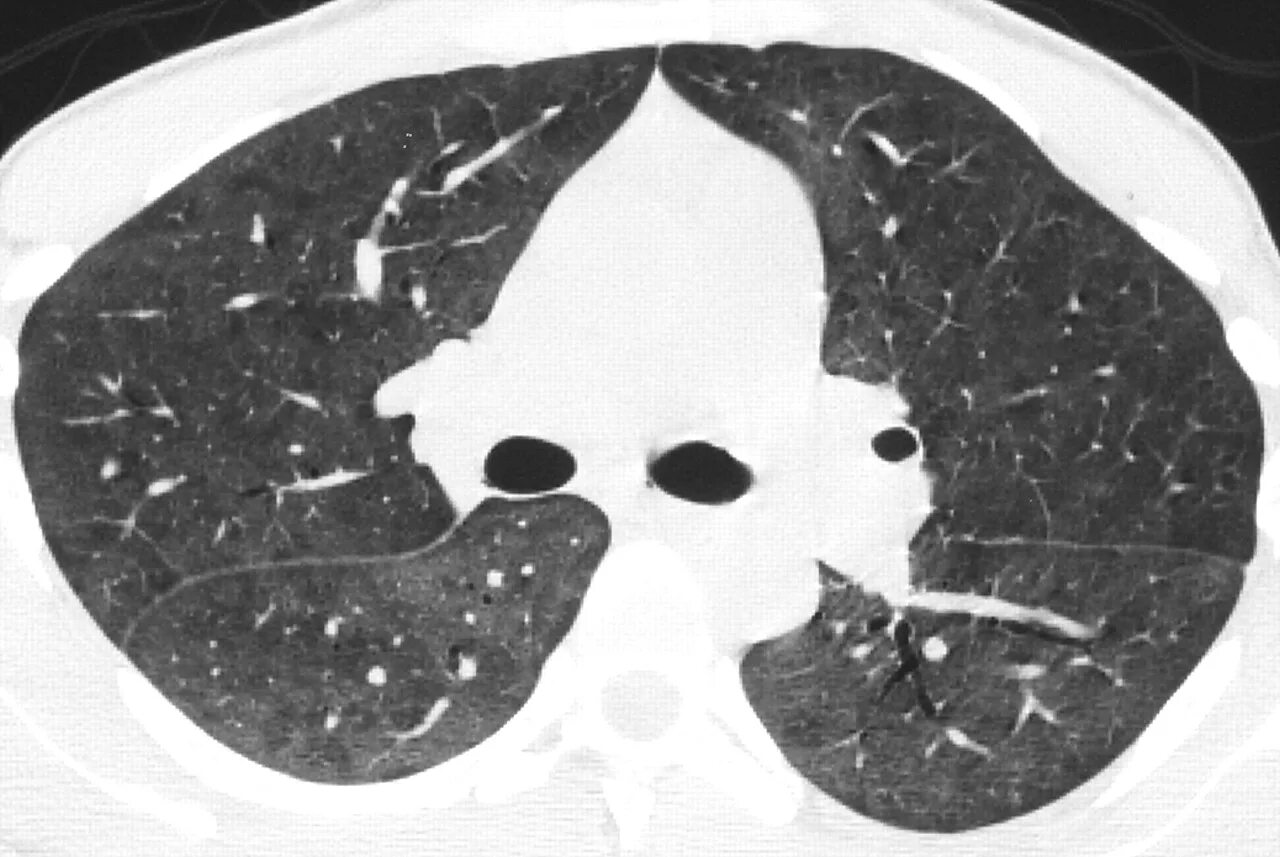

Мозаичная перфузия